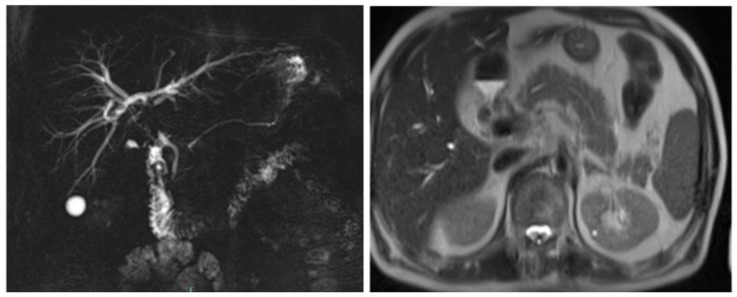

A 71 years old gentleman was admitted to hospital with a diagnosis of obstructive jaundice for further evaluation. He presented with 3 weeks history of vague abdominal pain, loss of weight (5 kg over two months) and appetite, generalized body itching and jaundice. He was a known case of Hypertension and Hyperlipidemia on medications. On examination the abdomen was soft, not distended, not tender and there was no palpable mass. The laboratory investigations were done (Table 1). On radiology, the MRI showed features suggestive of hilar periductal neoplastic pathology with obstructive biliopathy, focal inflammatory changes of the pancreatic head, few calcified lesions noted in the right diaphragmatic region and along the lateral margin of the splenic parenchyma (Figure 1: A and B). Based on MRI findings a diagnosis of Klatskin type IV tumor was reached and a management plan was made which include surgical intervention. However, before proceeding for surgery, IgG4 had been requested and found to be elevated. For the reason, the diagnosis of IgG4‐SC was made and he was started on steroid therapy leading to resolution of symptoms.

Figure 1(A and B): MRI showed Features suggestive of hilar periductal neoplastic pathology with obstructive biliopathy and focal inflammatory changes of the pancreatic head.